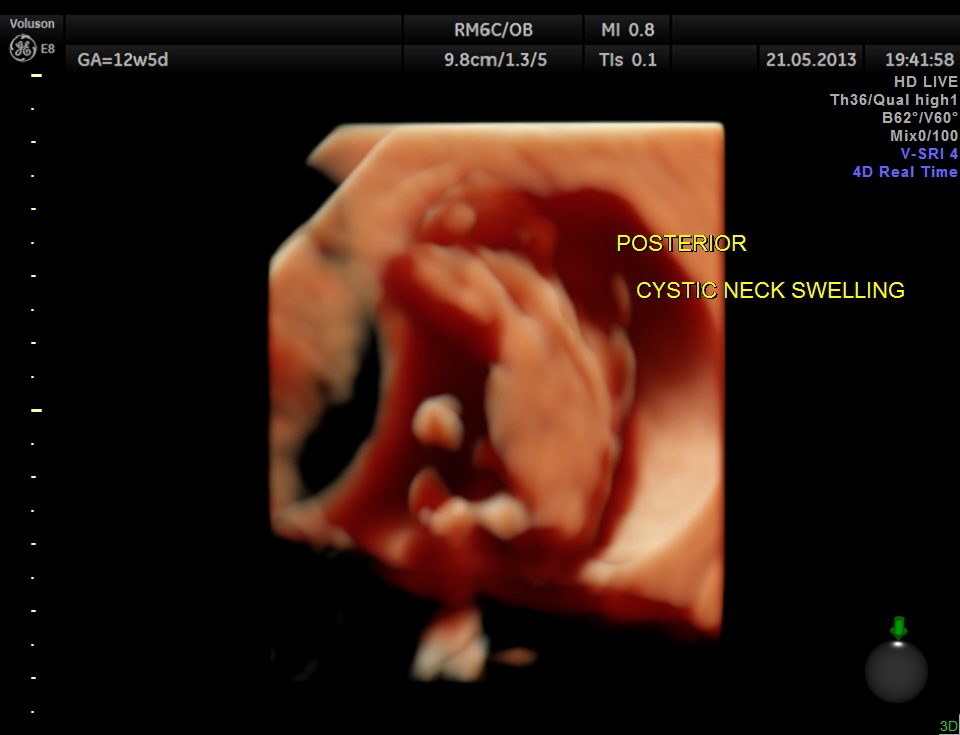

This 23 year old primi gravida, with no history of consanguinity was referred for 2nd opinion for evaluation of cystic swelling of the neck in the first trimester.

the following are high definition live images.

The diagnosis offered was cystic hygroma .

Cystic hygroma colli probably represent the most common cause for a neck mass detected prenatally. Other neck masses detectable ultrasonically include cervical meningomyelocele, hemangioma, teratoma, goiter, sarcoma, and metastatic adenopathy. Occasionally, a large cephalocele may mimic a neck mass. In most of these rare cases, polyhydramnios, hydrops fetalis, or other clinical features signal a careful search of the fetal neck.

1. Is the mass unilateral or bilateral, posterior or anterior ?

* most bilateral posterior masses are cystic hygroma colli, especially multicystic masses with a midline septation.